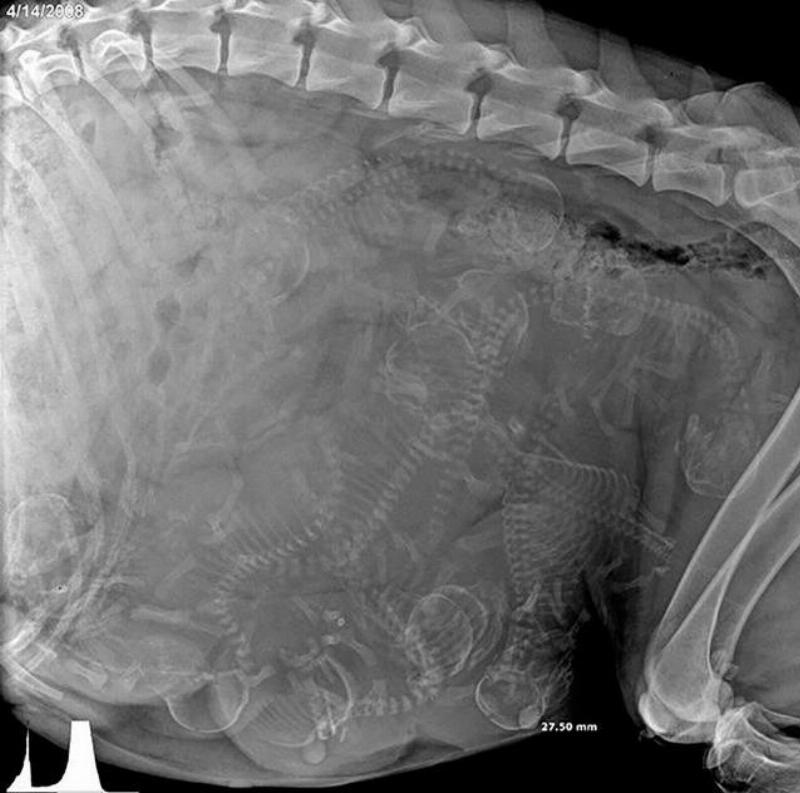

A Whole Bunch Of Puppies

This is an X-ray film that was taken of a pregnant dog.

If you look closely, you can see a whole bunch of puppy skeletons inside the mother dog's uterus.